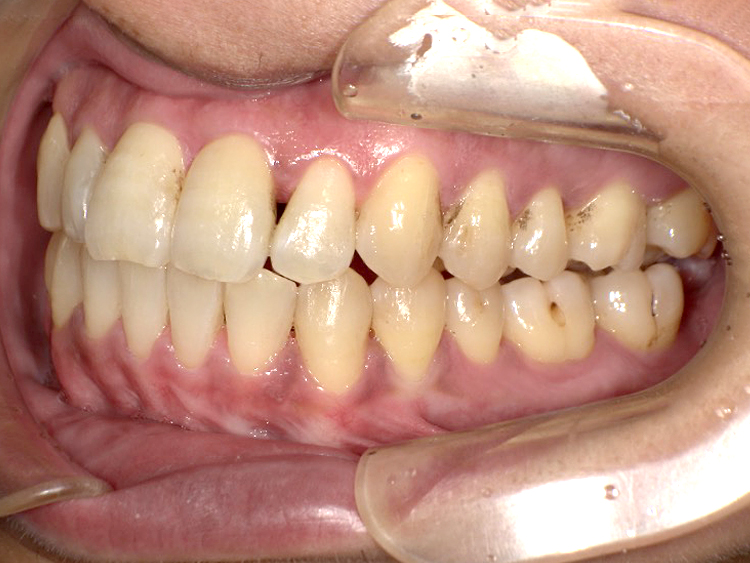

症例6

Before

After

| 主訴 | 噛み合わせが気になる |

|---|---|

| 年齢 | --- |

| 治療 期間 |

約2年11ヶ月 |

| 治療 内容 |

インビザラインコンプリヘンシブ 右上6番・左上6番ALLセラミッククラウン |

| 治療費 | ¥1,116,000(税込)/調整料含む |

| 治療のリスク | 歯を動かすことで、歯茎が下がるリスクある。 矯正終了後は、リテーナーを使用し、後戻りを防ぐ必要がある。 |